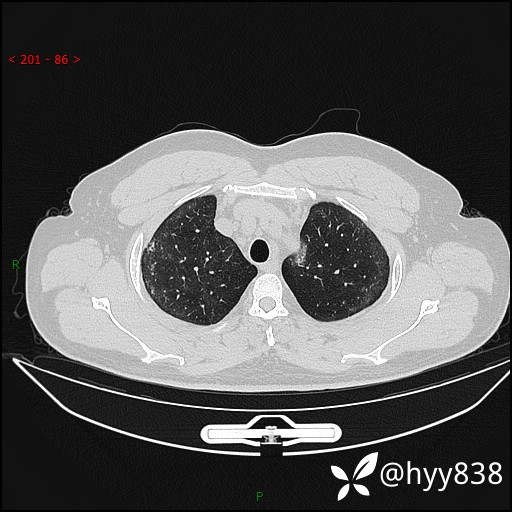

第一次胸部CT